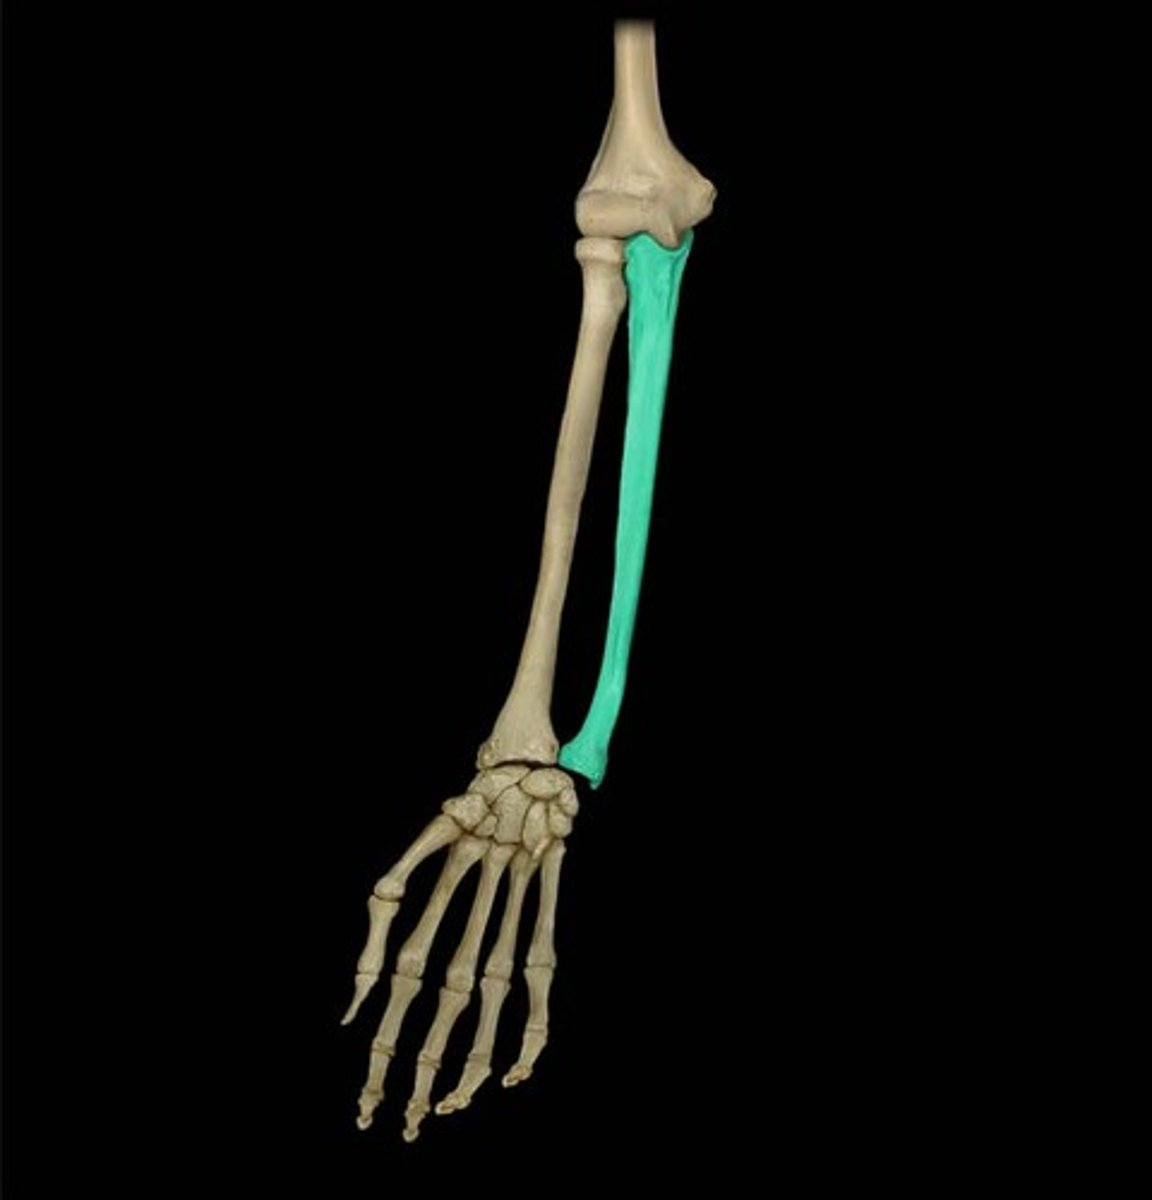

Radius

lateral bone of the forearm, in line with the thumb

Ulna

Inner and larger bone of the forearm, attached to the wrist and located on the side of the little finger.

Proximal radioulnar joint (PRUJ)

articulation between head of radius and radial notch of ulna; uniaxial pivot joint that allows for rotation of radius during pronation/supination of forearm

distal radioulnar joint (DRUJ)

articulation between the head of the ulna and the ulnar notch of the radius